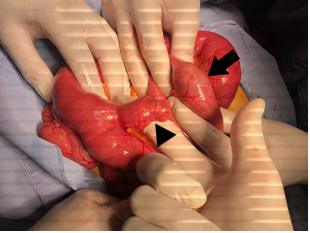

Laboratory tests showed electrolyte imbalance in 14 patients (87.5%) and liver function tests abnormalities in five patients (31.2%). A correct preoperative diagnosis of GI was reached in 13 patients (81.2%); the remaining was diagnosed during surgery. The classical image signs of GI were visualized in 7 patients (43.7%) on plain abdominal radiograph (Figure 1), in six patients (37.5%) on ultrasound (Figure 2) (Figure 3), and in 13 patients (81.2%) on CT (Figure 4) (Figures 5a & b).

Figure 2 Abdominal ultrasound shows a hyperechoic oval-shaped image of 3.6 cm with acoustic shadow suggestive of a gallstone located in the right lower quadrant of the abdomen.

During exploratory laparotomy, enterotolithotomy alone was performed in 11 patients (68.7%); two of such enterolithotomies were performed in the duodenum followed by simple duodenorraphy, due to poor clinical conditions of the patients. In one patient the gallstone was extracted through a gastrotomy. An intestinal resection and anastomosis was needed to extract the stone and remove an ischemic ileum segment in one patient. In the remaining 12 patients the procedure was completed with enterotomy and transverse enterorraphy (Figure 10). A Meckel´s diverticulum was incidentally found in an 81years-old female but since it was not complicated, no surgical management was needed (Figure 11). One-stage-procedure was performed in 5 patients (31.2%). No patient was managed with a two-stage procedure. Median intraoperatory blood loss was 110ml (range 40-350), median surgical time was 100minutes (range 53-230), and median hospital stay was 7 days (range 1-17).

Figure 10 Surgical findings in a patient with gallstone ileus. Enterotomy performed over the site of the impacted gallstone in the terminal ileum.

Figure 11 Surgical findings in patient with gallstone ileus. a. Segment of ileum at 60cm from the ileocecal valve with non-complicated Meckel´s diverticulum (arrowhead) and site of impacted gallstone in ileum, at 50 cm from the ileocecal valve (arrow).